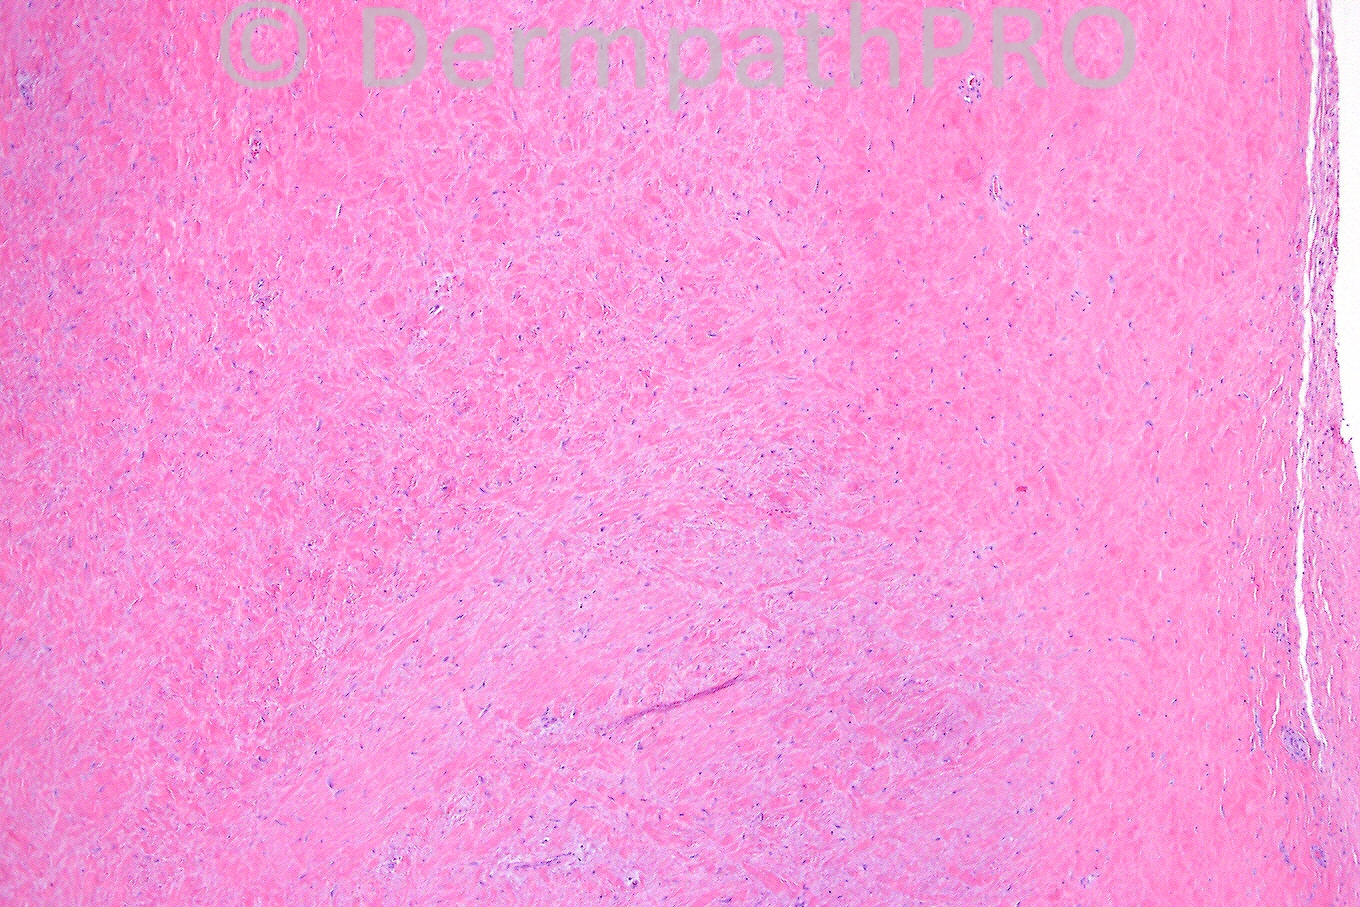

Female 46 years, subcutaneous nodule on upper arm.